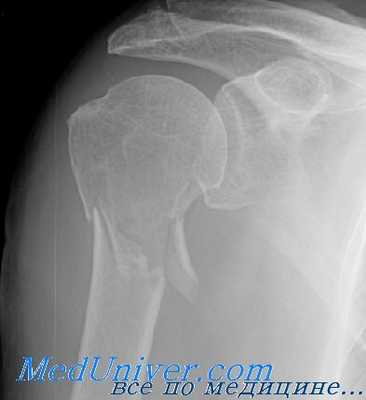

(Слева) На передне-задней рентгенограмме определяется перелом хирургической шейки. Сложно сказать, является ли медиальный край головки плечевой кости отдельным отломком перелома или остеофитом.

(Справа) На 3D КГ с реконструкцией у этого же пациента определяется перелом хирургической шейки и подтверждается, что медиальный край является большим остеофитом.